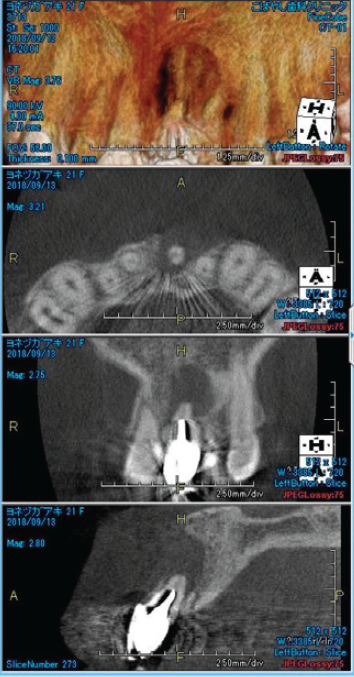

左下大臼歯部の急性炎症を主訴に来院(図16・17・18)。

緊急処置を行い、基礎資料を収集し問題点を抽出し、総合診断治療計画を立案し、患者に説明した。臼歯部に歯科治療が繰り返されている原因の一つに咬頭嵌合位が安定せず、咬合干渉が認められる病的咬合が挙げられる(図19)。臼歯部に応力が集中し、補綴装置やセメントが安定せず歯冠部からの漏洩によって根管内が感染していることも予測できる。包括的な見地から、咬合治療を行うために矯正治療の必要性を説明し承諾を得た。

矯正的診断は上下顎骨劣成長と骨格性開咬を伴うAngleⅡ級症例。矯正治療の目的は前歯の叢生の改善と適正な被蓋関係の確立。治療計画は上顎両側第一小臼歯を抜歯し、上顎前歯の叢生の改善と下顎両側第二小臼歯を抜歯し、下顎両側大臼歯を近心移動し、咬合高径を調整し前歯部の被蓋関係を改善する。初期治療にて炎症のコントロール、主に感染根管の再治療を行い(図20)、矯正治療に入る(図21)。矯正治療により歯のポジションが改善した後、プロビジョナルレストレーションにてリハビリテーションを検証し(図22)、最終補綴処置を行う(図23)。臼歯部の環境が改善された事で、臼歯への力の集中による失活歯の歯根破折の可能性の減少と根尖周囲の歯周組織の安定を確立できた。

<術前左下6・7のレントゲン像>

主訴の歯であり、根尖部に広範囲に渡って透過像を認める

歯質は十分に保存されていることが予測される

(図16)

<左下6・7術前CBCT像>

根尖周囲の骨欠損が著明で舌側皮質骨の開窓も予測される

(図17)

<左下6・7術後CBCT像>

術前のCBCT像と比較して

根尖部周囲組織の再生が確認でき、

歯の保存は可能と判断した

(図18)